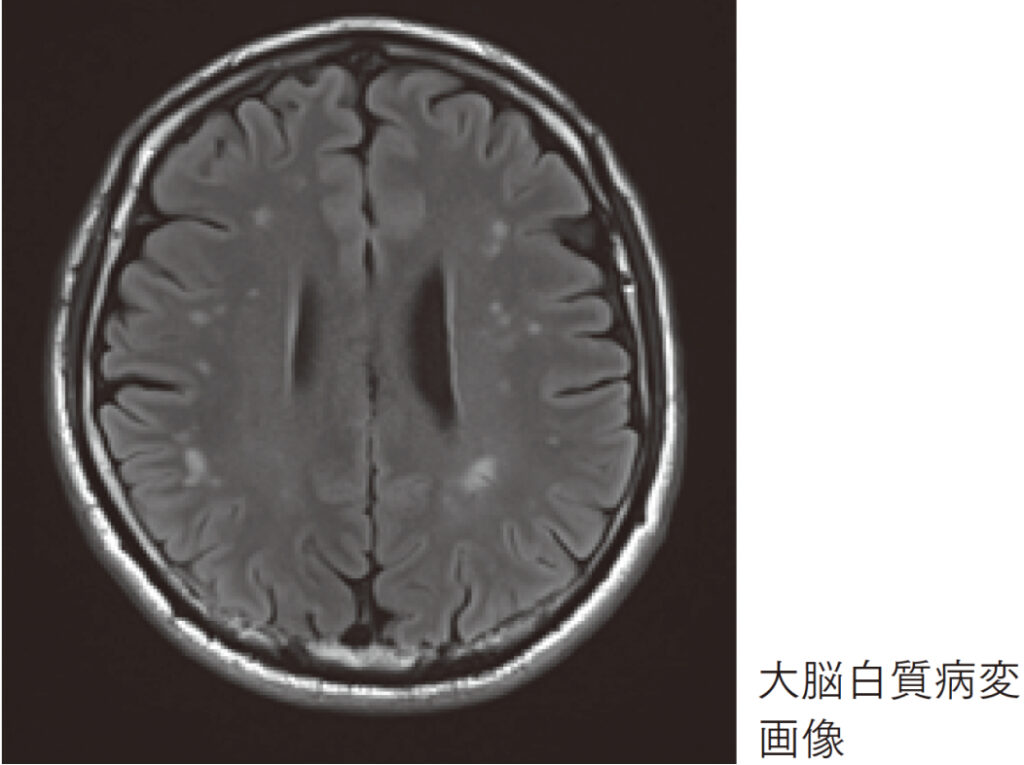

宮崎:当院の脳ドックを受けた方の中に「白質病変」と指摘される方が数多くいらっしゃるのですが…。

金山:白質病変とは大脳白質に起きた虚血のことです。白質病変の多い方は少ない方に比して脳卒中のリスクが高くなると言われており、今後の発症リスクの予測になると思います。

宮崎:白質病変のある方は、高血圧や高脂血症などの病気を合併していることも多いです。生活習慣病が増える40歳くらいから注意が必要ということですね。

金山:ある年にワンポイントで見るのではなく、経時的に進展を見ていくことが大事です。